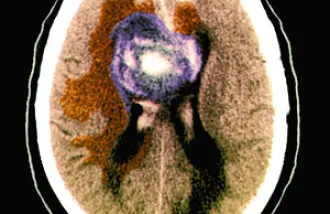

Brain tumors form synapses with healthy neurons, Stanford-led study finds

Tumors called high-grade gliomas wire themselves into the healthy brain, receiving and interpreting electrical signals from normal neurons, a Stanford study has found.

Deadly brain cancers act like 'vampires' by hijacking normal cells to grow

Researchers are beginning to understand why certain brain cancers are so hard to stop.